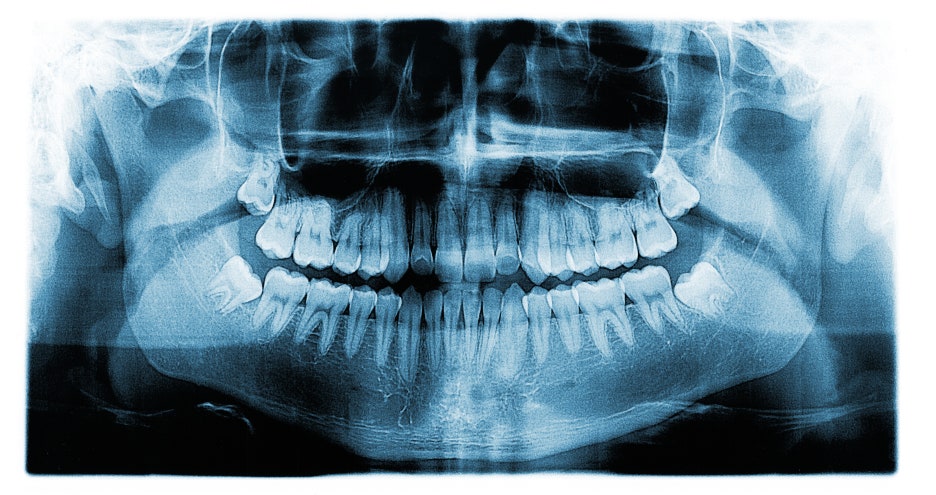

제 3 대구치가 뭘까요? 우리가 어금니라고 부르는 치아는 제 2대구치까지 있었어요. 그렇다면? 네 맞습니다 바로 사랑니였어요. 가장 늦게 돋아나는 치아였어요. 인간의 구강은 다양한 종류의 치아로 이루어져 있다고 했어요. 이러한 치아들은 기능과 역할이 다 다른데요. 함께 맞물려 작동해 일상적 생활을 도와준다고 했어요. 영유아기 때부터 윗니 아랫니 각각 10개씩 20개를 가지고 시작합니다. 이를 유치라고 부르는데요. 만 6세부터 하나씩 영구치로 교체되기 시작한다고 들었어요. 만 12세 정도가 되면 영구치가 다 자라게 됩니다. 이렇게 전체적인 치아 개수는 사랑니를 포함해 보통 32개입니다.

만약 위 아래 사랑니를 전부 제거한다면 28개를 가지게 된다고 했어요. 그래서 전체적인 치아의 수를 셀 때는 28개를 기준으로 했어요. 사랑니의 위치와 형태, 개수는 개인마다 달랐어요. 제 3 4대구치의 원래 기능은 아주 질긴 음식 등을 씹을 수 있게 하는 것 이었습니다. 음식이 부드러워지고 곡물 위주의 섭취가 주가 되면서 아래턱이 작아졌어요. 그래서 사랑니의 공간이 부족해 문제를 일으켰다고 할 수 있었어요. 너무 크게 발달하거나 잇몸, 뼈 속에 자리잡고 썩을 경우 인접한 치아나 잇몸에 문제를 일으킨다고 했어요.